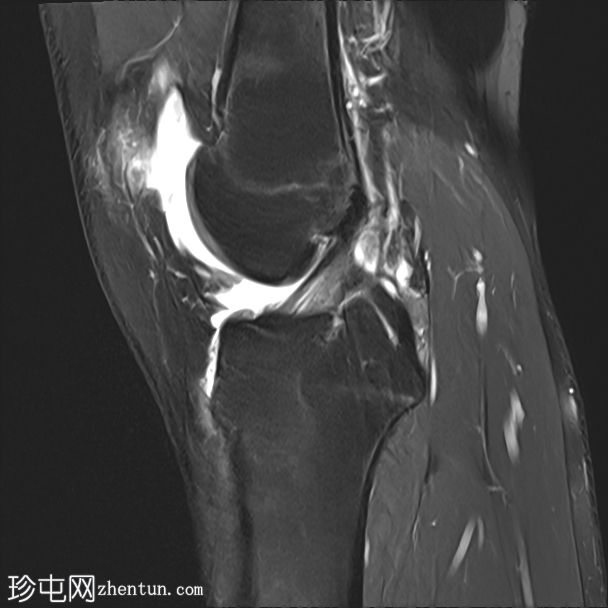

冠状位PD序列

脂肪抑制序列

内侧髌股韧带撕裂,伴外侧髌骨半脱位。

内侧髌骨缘可见骨髓水肿和一小块皮质撕脱碎片,内侧髌骨关节面存在全层软骨缺损。

外侧股骨髁轻度骨髓水肿。

内侧副韧带和外侧副韧带II级损伤。

膝关节积液

这些影像学表现是滑车发育不良的典型特征,滑车发育不良是髌骨不稳定的最常见病因,尤其是复发性髌骨外侧脱位。